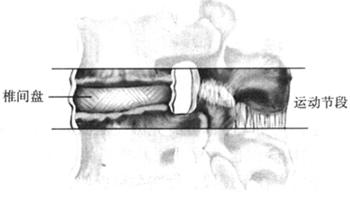

图1-26 椎间盘为运动性软骨关节

椎间盘不但是椎体间主要的坚强联系与支持结构,同时也是脊柱运动和吸收震荡的主要结构,起着“弹性垫”的作用,能承受身体的重力,将施加于脊柱的力吸收并重新分布(图1-33)。椎间盘能保护和控制脊柱各种活动,有平衡缓冲外力的作用。椎间盘受到压缩或牵引后,能很快恢复原来形状(图1-34)。随体位不同,椎间盘承受的压力也发生相应的改变,一般在坐位时最大,直立位较小,卧位最小。

每个椎间盘及相邻椎体及骨突应视为-个运动单位,具有一定动力及机械功能。一个运动单位发生紊乱必然影响邻近运动单位。椎间盘的弹性及张力取决于软骨板的通透性和髓核的渗透性。椎间盘的吸液性如发生改变,不仅影响椎间盘的稳定性,而且可使椎间盘发生变性,椎间隙变窄,其后部椎间关节及椎间管必然受到影响(图1-37)。